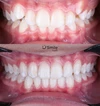

Zirkonyum uygulamalar

Porselen uygulamaları

Laminate veneer